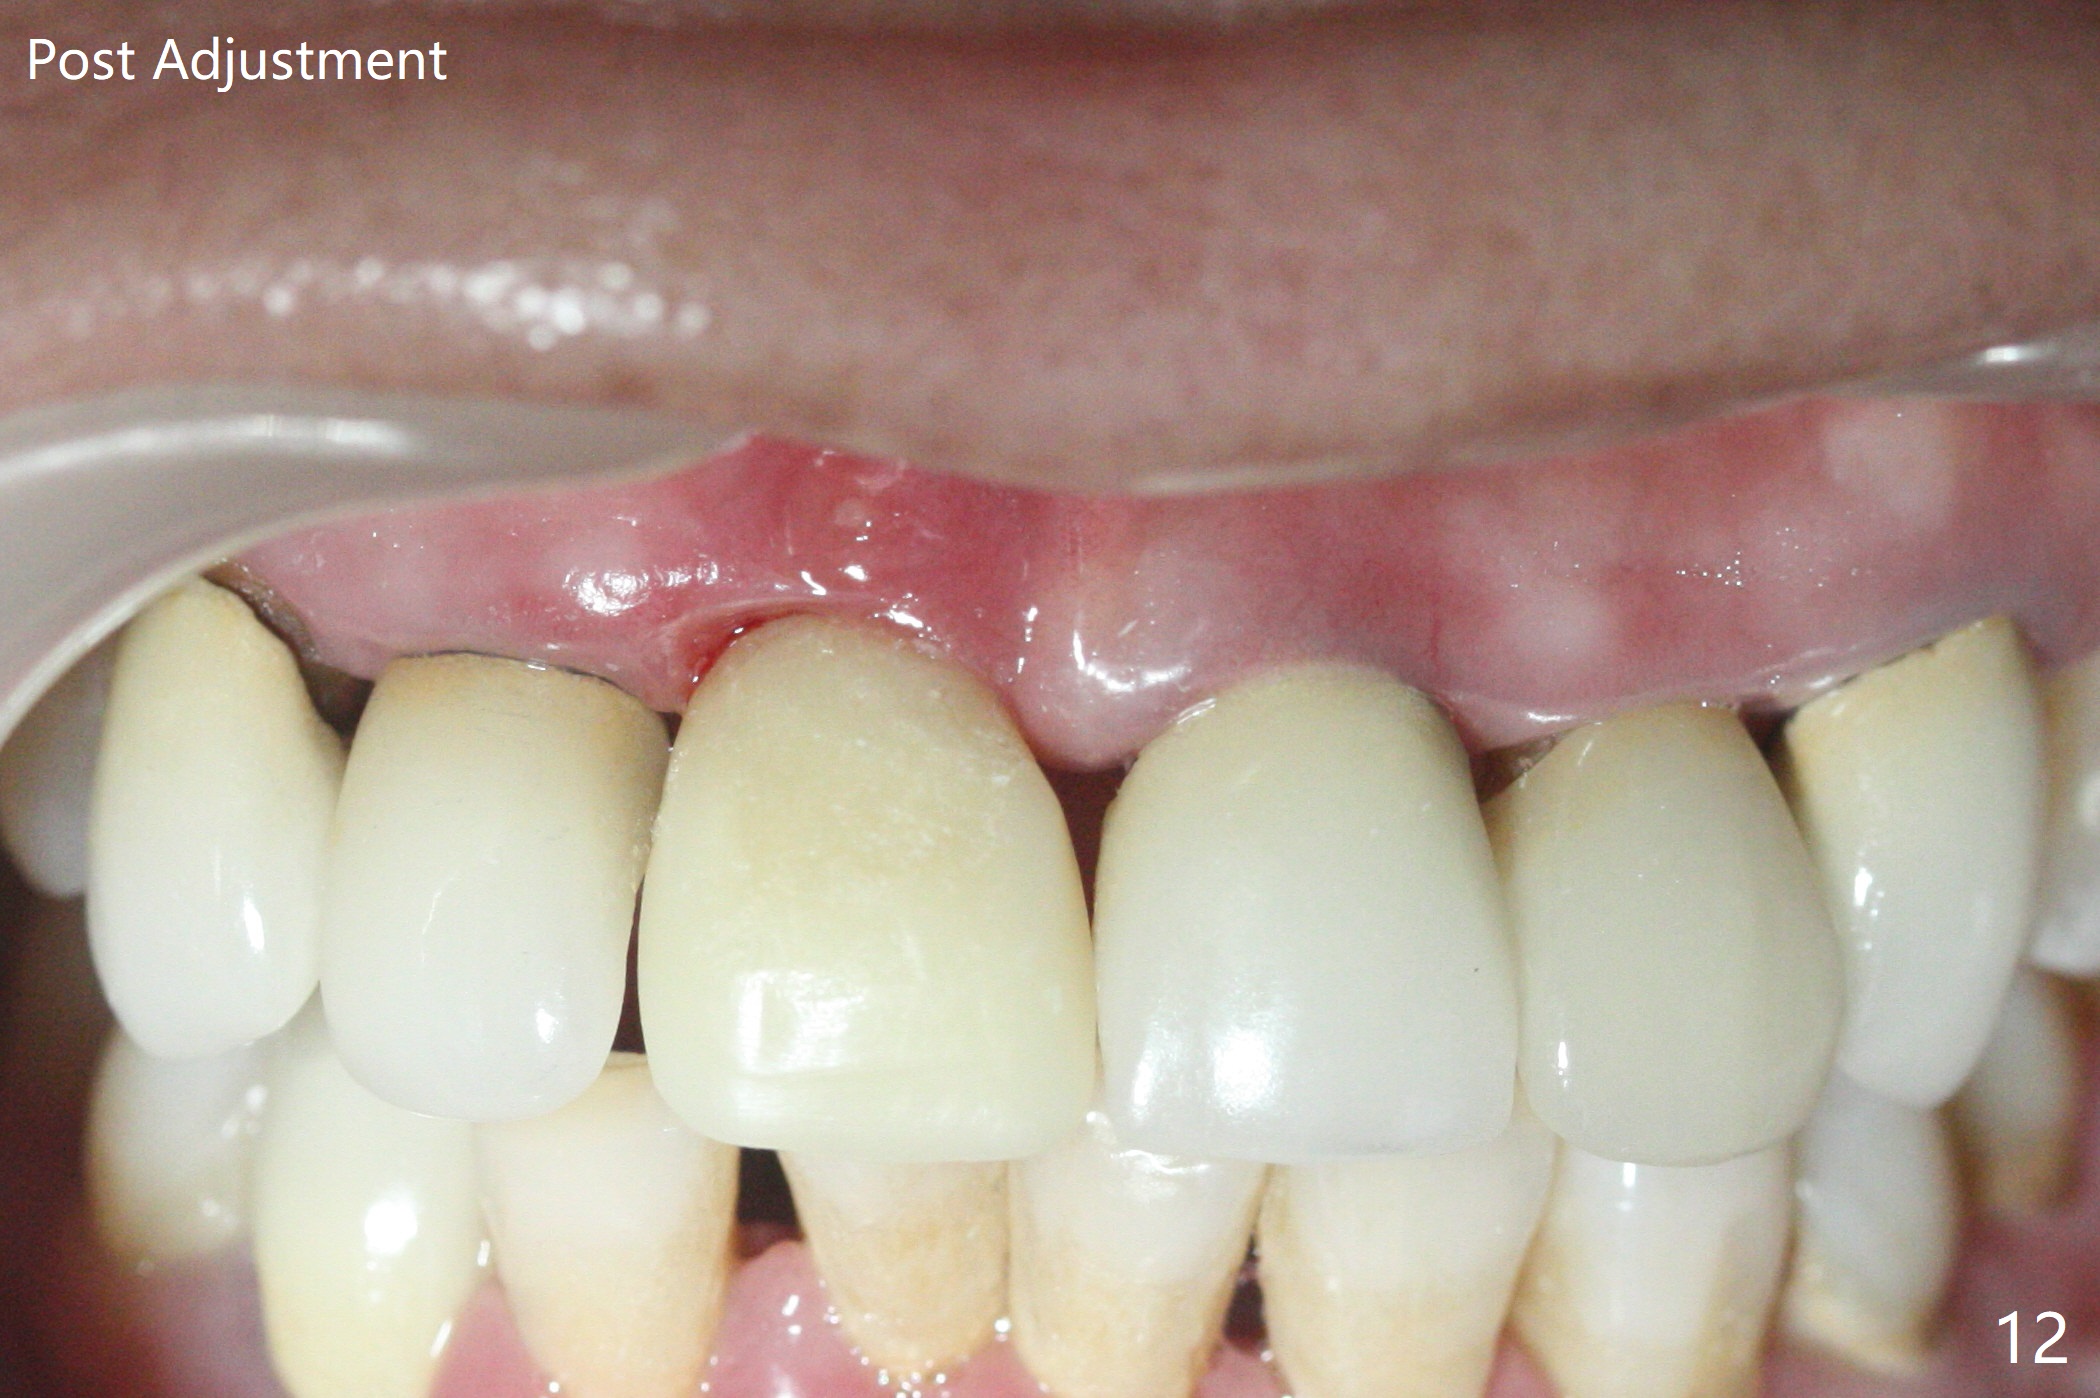

徒手初步钻洞显示方位不对(图一),重新钻洞方位尚可,好像接近鼻底(图二:红线);植入3x11.5毫米一段式植体(图三),3-5个螺纹暴露,植体似乎接近鼻底;旋转植体三趟,植体仿佛卡人鼻底,扭力大约35Ncm,植入粘性骨粉(图四,五:*)前,塞入PRF膜,紧贴颊侧粘膜,促进瘘道愈合。骨粉不仅围绕植体,而且紧贴邻牙牙根(图六(第二轮植骨:overgrafting):<)。病人术后第二周开始使用水牙线,术后三周牙龈健康多了,瘘道消失(图七)。术后六周颊侧骨壁开始塌陷(图八:>),临时牙冠颊侧颈部显得隆起(*)。调整后,牙冠外形改善(图十一至十三),取模前颊侧牙龈缘有可能下降,两个中切牙龈缘可能一致。术后3.5个月骨粉形态(图十四)与术后即刻(图六)有所不同。颊侧牙龈仍红肿轻度触痛(图十五),可能因为临时牙冠不利于局部卫生,所以决定取模制作永久性牙冠。粘固时使用临时胶水,并且涂抗菌素。另外一个可能因素是颊侧骨板薄(图十六:*),细菌感染植体螺纹,永久性牙冠粘固前,拍摄CT(放置cotton roll),必要时,植骨。永久性牙冠远中有缝隙,为了预防病人后悔,使用临时性粘固剂固定(图十七)。Return to No Caries DIO 下一个病例 一段式植体边缘制备 导板与内提升 Xin Wei, DDS, PhD, MS 1st edition 12/22/2020, last revision 06/15/2021